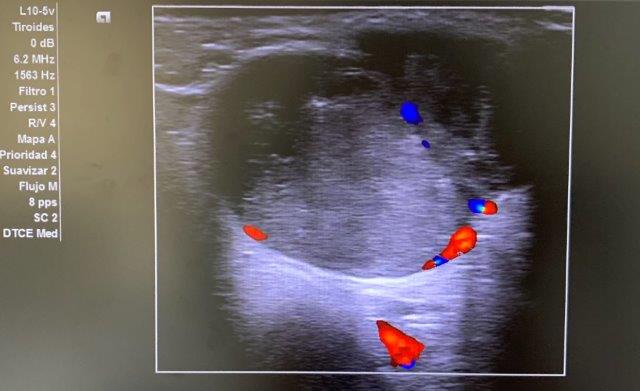

ECO POCUS: imagen isoecoica, heterogénea, redondeada con captación periférica de Doppler, que mide 26.9 x 21.7 mm (corte transversal) y 30.3 mm (corte longitudinal). Vemos un bultoma originado en la cola de glándula parótida.

Ante los hallazgos ecográficos y la persistencia del bultoma, orientamos juicio clínico hacia posible tumoración originada en parótida, con características mixtas de benignidad-malignidad (clínica + ecografía).